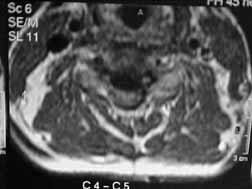

MRI-C-5/C-6

Disc prolapse